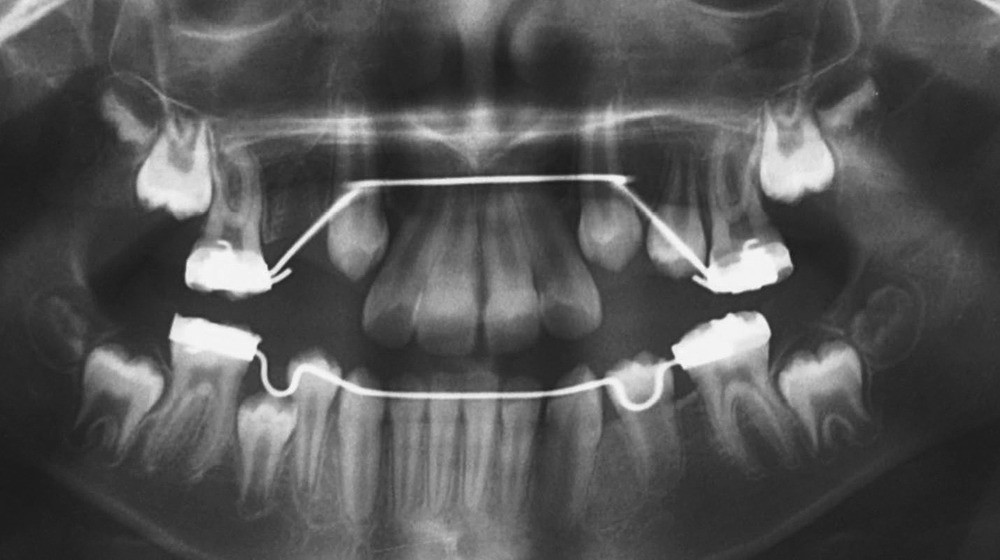

Lina, 8 ans et 5 mois, nous est adressée en consultation d’orthodontie dans le service de médecine bucco-dentaire de l’Hôpital Bretonneau en transfert avec absence des 2 prémolaires du secteur 1, alors que 44 et 45 sont présentes et que cette dernière manque de place pour faire son évolution sur l’arcade (fig. 1 et 2).